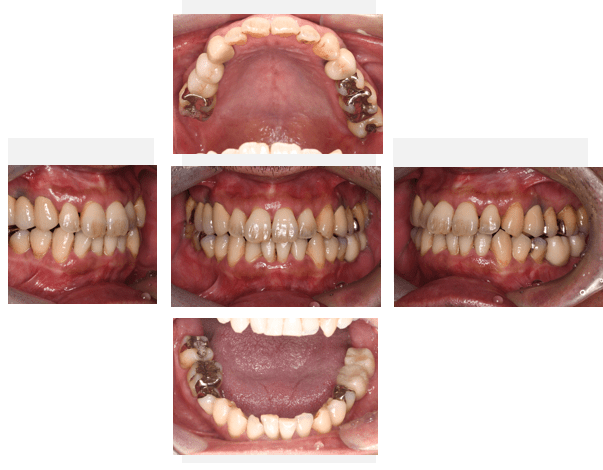

口腔内写真

- Befor

- After

| 年齢 | 50代・男性 |

| 主訴 | 左上7番 左下5番7番 |

| 治療内容 | ・インプラント埋入 ※1:GBR(骨造成)・・・骨再生誘導法。骨の高さや厚みを人工骨や人工膜などを使用し再生する方法 |

| 治療費 | 合計:1,809,500円(税込) ■内訳 ・左上7番 ・左下5番7番 |

| 治療期間 | 左上7番約1年 左下5番7番約10ヵ月 |

| 治療方針 | 左上7番は昔他院で被せものをしており、被せものの中が歯ぐきの中まで虫歯になっていたため抜歯せざるを得ない状態だった。抜歯と同時に骨造成を行い、骨が出来るまで4ヵ月待ってからインプラントを埋入した。 ※2ポンティック・・・歯のない部分を補うダミーの歯。 |

| 担当者所見 | 元々金属の被せものが多く入っていたため、2次カリエス※3が多かった。今回は金属ではなく、ジルコニアを使用し、2次カリエスにならないよう、患者様にはブラッシング指導とメンテナンスの重要性をお伝えした。 ※3二次カリエス・・・詰め物や被せものを入れた歯が虫歯になること。 |